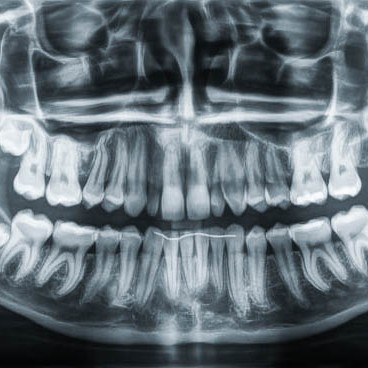

3D Röntgen DVT

Für radiologische Untersuchungen mit speziellen Fragestellung im Dental- als auch HNO- Bereich, bietet das DVT (digitale Volumentomographie) das genaueste Aufnahmeverfahren. Die 3D Röntgendarstellung kann sowohl zur Fokussuche bei Beschwerden, Wurzelkanalbehandlungen als auch bei chirurgischen Planungen genutzt werden. Für eine chirurgische Behandlungsplanung mit Implantaten ist dieses Verfahren der neueste Standard.